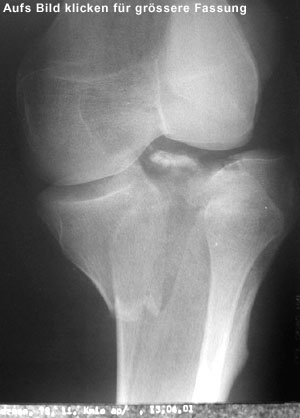

Auf dem Computertomogramm (3D-Rekonstruktion des Schienbeinkopfes bzw. Tibiaplateaus) sieht man schön die Bruchstelle des grossen Knochenfragmentes. Dummerweise geht der Bruch mitten durch die Kniegelenkfläche. Dazu kam noch ein sogenannter Impressionsbruch, hier nur für Profis erkennbar: Ein Teil der Gelenkfläche wurde durch die Gewalt des Sturzes in den Knochen hineingepresst.

Leider kommt das wegen der Beschaffenheit des Knochens nicht von selbst wieder hoch und musste angehoben sowie durch eine sogenannte Spongiosaplastik festgemacht werden (Knochenmaterial wurde aus dem Beckenkamm entnommen und im Knie unter das eingedrückte Stück wieder eingesetzt).

Als Vergleich: Wenn man den Finger in ein Stück Styropor drückt, bleibt auch ein Loch zurück. Dazu waren auch die Kreuzbandansätze angerissen.